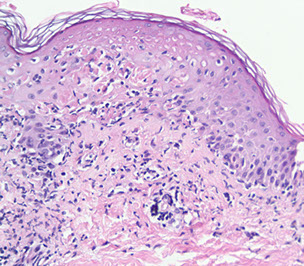

"Fingers" that point down are rete ridges, with papillary dermis (pink hyaline) right next to it, and a dermal papilla interlocking with the rete ridges (with  little capillaries in them)

Epidermal layers

From top to bottom:

Corneal layer (Stratum corneum) - extra barrier against entry into body, dead cells on top, flake off

- acral skin usually has a thick corneal layer (in addition to the lucidum layer)

Stratum Lucidem - hot pink layer beneath the corneum that is only seen on acral skin (the palms and soles), or as protective mech on skin that has been rubbed too much

- below corneum and above granulosum, only seen on the palms and soles and skin that has been rubbed too much

Granular layer (Stratum Granulosum) - when cells from spinosum start to pick up keratohyaline granules (have loracrin and involucrin little purple granules) that help keratinocytes die and lose nucleus to become skeletons in the corneal layer (stratum corneum)

Stratum Spinosum - little spines, desmosomes bwt cells

- due to shrinkage during processing, cells in the spinosum usually have a halo directly around the nucleus (bc their desmosomes are locked into a network) vs melanocytes that have cytoplasm around their nuclei and sometimes a space around the cytoplasm, bc they are not locked in by desmosomes

Keratinocytes usually have pigment on top of their nuclei, in the direction of the corneum, to protect them from the sun

Stratum Basalis - where stem cells reproduce squamous cells, pushed upward; pink bc filled c keratin

Epidermis, arrow pointing to stratum Lucidem,

Arrow to pink papillary dermis, to the left is a rete ridge, to the right, an interlocking dermal papilla